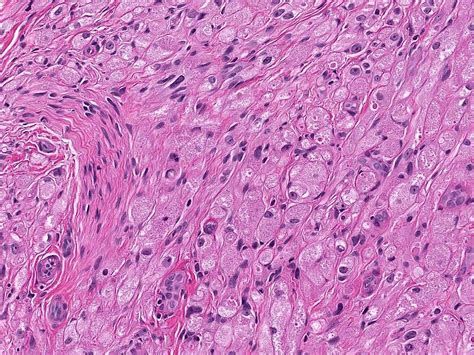

The histopathological features of granular cell tumours are distinctive and play a crucial role in their diagnosis. Key features include:

• Large, polygonal cells with abundant granular cytoplasm

• Small, centrally located nuclei

• Abundant lysosomes within the cytoplasm

• Positive staining for S-100 protein, a marker for neural and melanocytic differentiation

These features help differentiate GCTs from other types of tumours, such as rhabdomyomas and alveolar soft part sarcomas, which may have a similar appearance but different clinical behaviours.